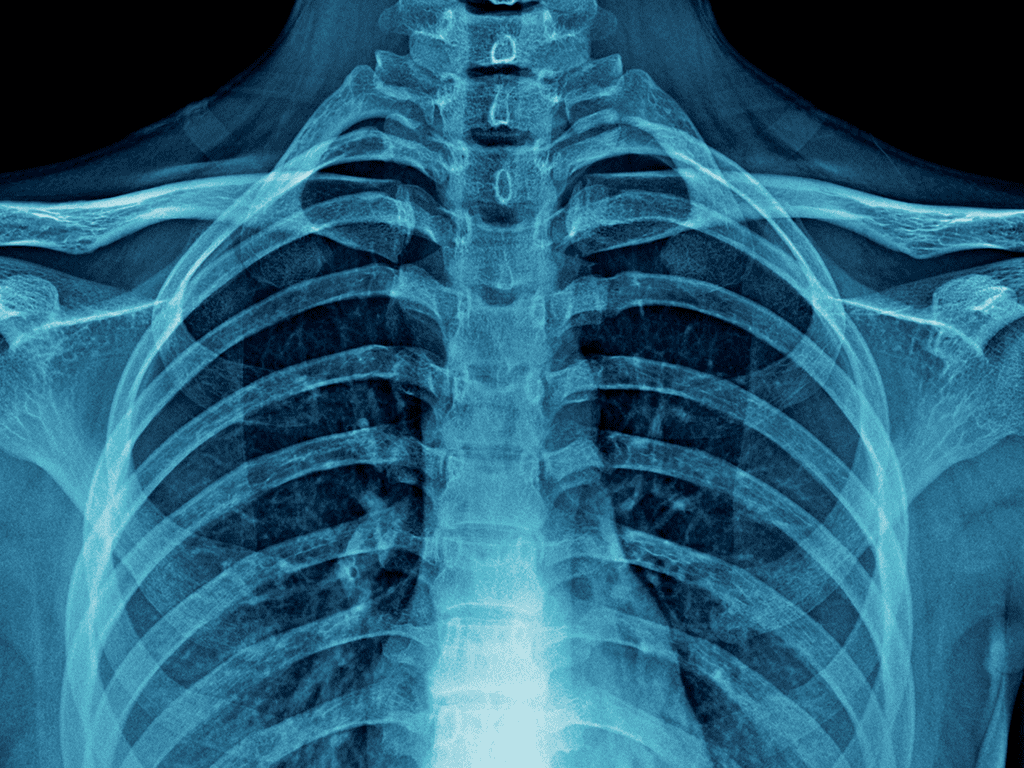

Fast and easy imaging is a big part of getting care and healing quickly. Patients can stroll into clinics that offer digital solutions and get high-resolution results right away, without having to wait long. If you require xrays in murrieta, today’s diagnostic technology gives you quick results that you can trust. No need to make an appointment; help is available right away when you need it most.

Digital x-rays do more than just speed things up; they also make things more accurate, flexible, and less harmful. Patients have a better experience when getting a diagnosis.

Modern systems are made to make fewer mistakes and improve visual data. For xrays in murrieta, facilities that offer digital solutions give the best clarity and fewer repeat scans.